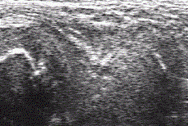

Начиная с 12 месячного возраста при стандартном сканировании вдоль пупартовой связки, на 1см ниже визуализировалась головка характерной сферичной формы (рис.3); В норме ядра окостенения были хорошо развиты, при сканировании визуализировались в виде гиперэхогенных структур.

Рис.3.Сонограмма тазобедренного сустава у ребенка 1,5 лет. (стандартное сканирование)

тазобедренный сустав патология дети

Ширина головки у детей в возрасте 1- 1,5 года равнялась 12,06+0,33мм, «щель сустава» 4 + 1,1 мм (показано крестиками). Показатели хрящевого покрытия Н-1 и H-2 (характеризующие запас со стороны ацетабулярного аппарата в процессе роста) при продольном сканировании были не менее - 0,5 мм. Отсутствие своевременной диагностики и адекватного лечения приводило к выраженной децентрации головки - вывиху бедра. В таких случаях головка бедренной кости при стандартном сканировании не визуализировалась.